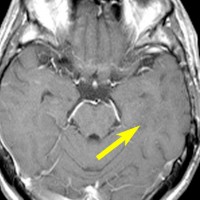

軽度の左下肢の麻痺で発症した50代の患者さんです。一見,かつてのグリオマトーシス gliomatosis あるいは diffuse hemispheric glioma WHO grade 4 のように見える非常に広範囲な病変です。しかし,病理診断は 星細胞腫 IDH mutant WHO grade 2でした。

放射線治療によく反応し,片麻痺は消失して,画像上の腫瘍高信号もほぼ消失しています。